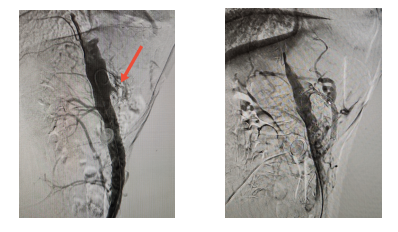

面对这一高难度挑战,何创业主任带领卫飞鹏医生等团队成员,凭借丰富的复杂钙化病变处理经验,术中精准操控导丝,成功穿透坚硬钙化斑块,顺利开通闭塞的肠系膜上动脉,并采用高压球囊充分扩张后,精准植入支架,成功重建肠道血供“生命线”。

手术效果立竿见影。术后第二天,困扰患者长达一年的腹痛症状即完全缓解,食欲逐步恢复。术后一个月随访显示,李奶奶体重已回升10余斤,精神状态明显改善,生活质量显著提升。